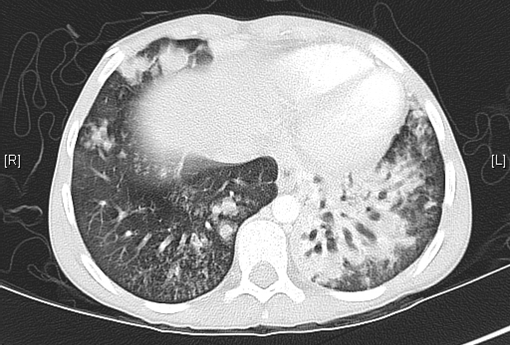

Figure 4

How do you interpret the CT image?